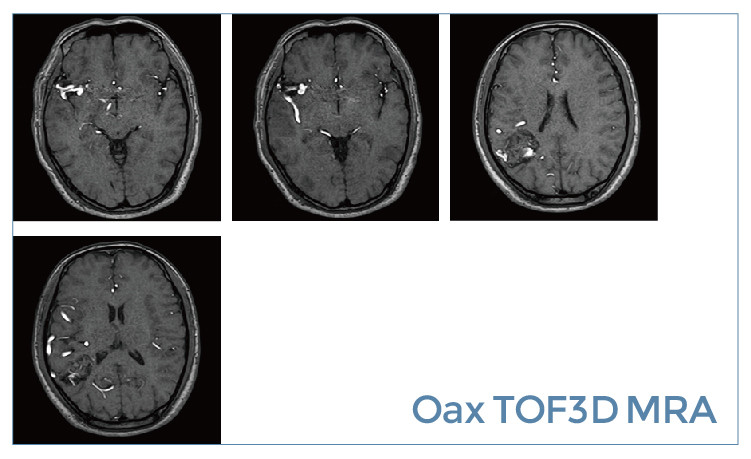

【朗润影像档案】20190531磁共振影像病例结果讨论

2.jpg3.jpg